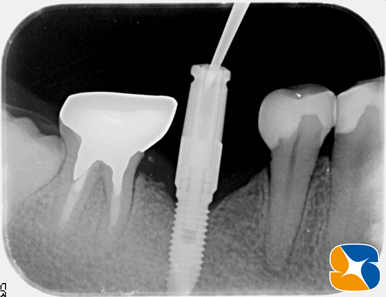

砕けた歯根を抜歯した後、続けてインプラントを同日に移植しました。

CGFと骨の誘発材(β−TCP)を使って、アゴ骨と歯肉の早期再生・回復を促しました。

使用インプラント:スプライン直径3.75㎜、高さ11.5㎜